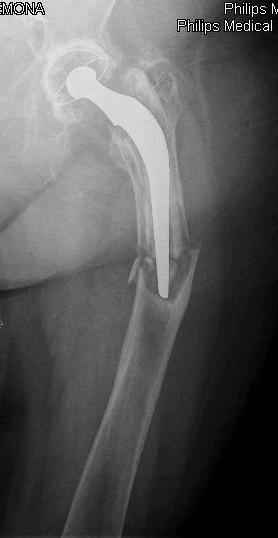

Reminded me of a case I did a couple years ago - 30 year old woman with juvenile rheumatoid arthritis and a nonunion below her stem. Fixed with retrograde nail which docked with the stem and a lateral locking plate. Image attached. One of the companies should come up with a stem design and nail system that anticipates this need.